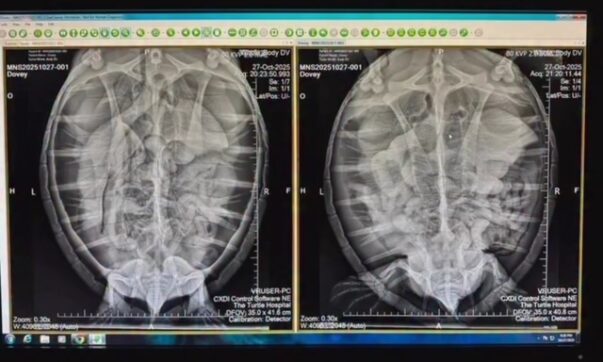

- 10/27/2025 – Meet Dovey! a juvenile green sea turtle rescued this week in the Florida Keys. She was found floating and lethargic. X-rays revealed air in her coelomic cavity and blood work is showing unstable blood glucose levels. Dovey received a procedure where her coelomic cavity was tapped to remove the excess air … you can see improvement in the x-rays in “Dovey Photos”